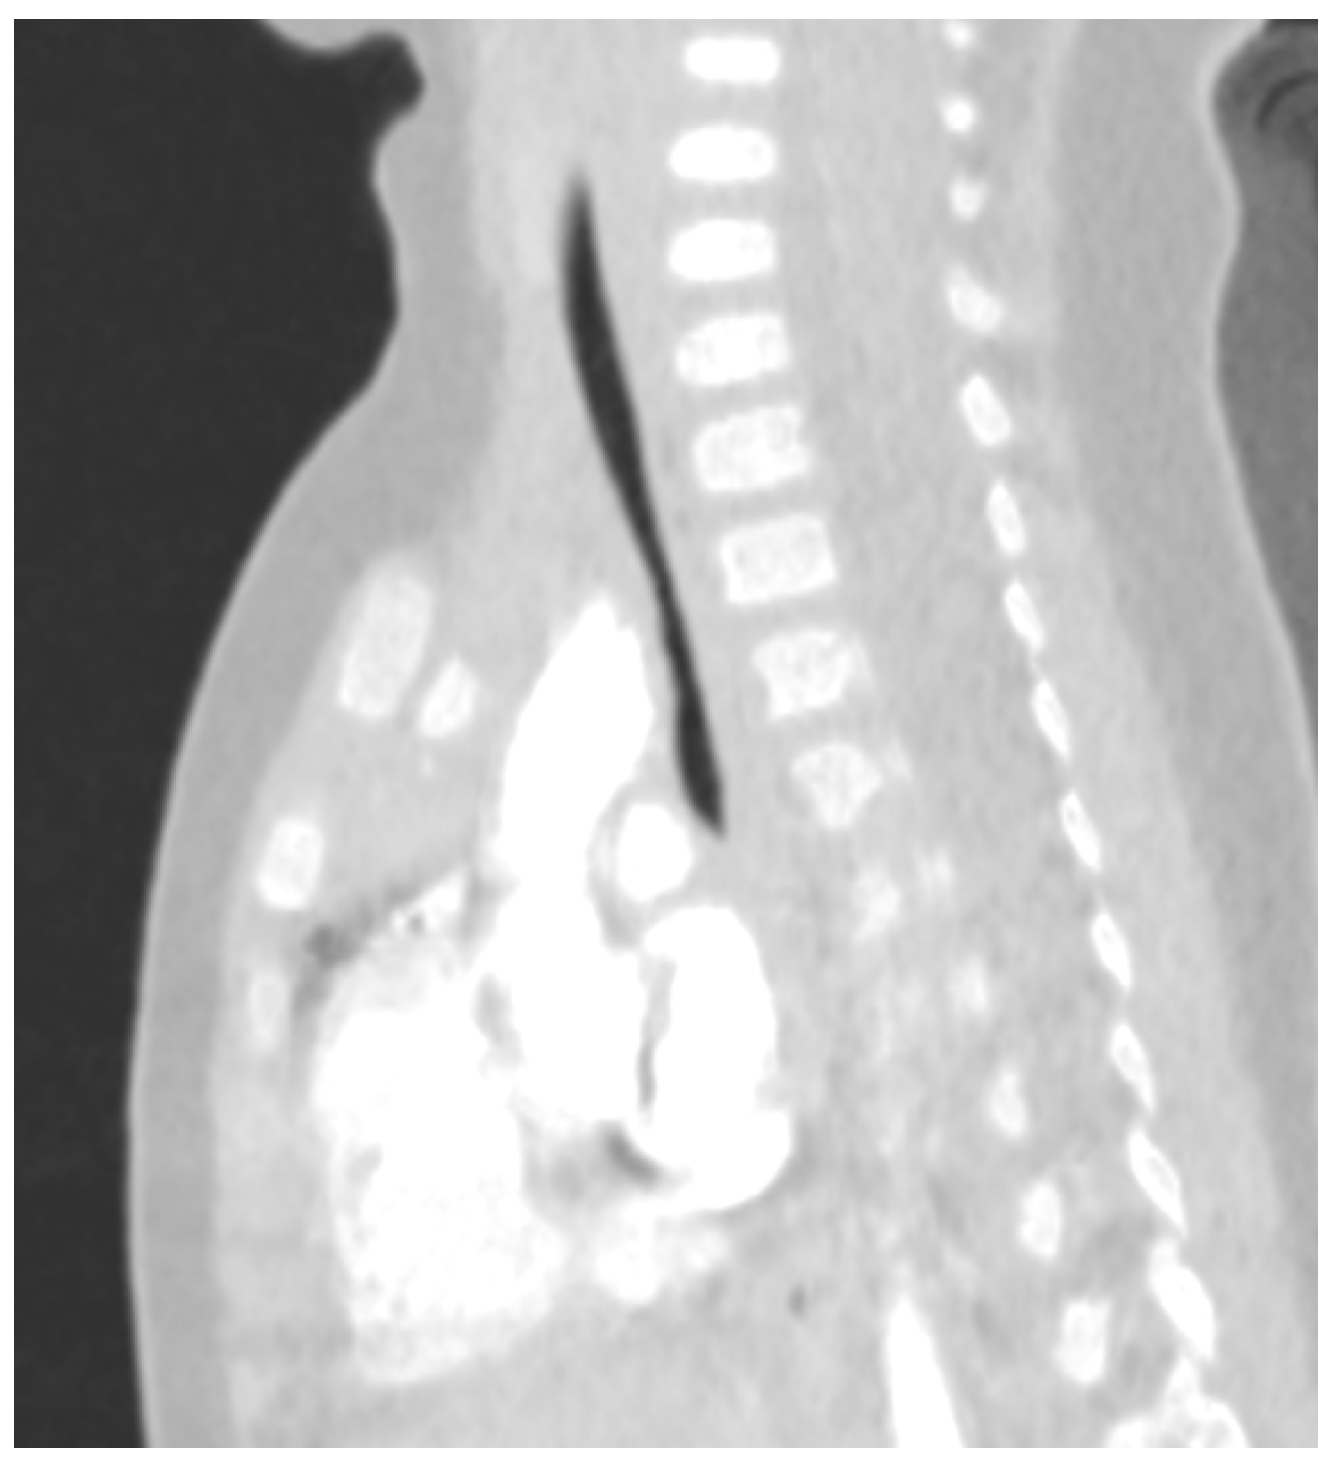

4.1. Airway Malformations

- Fockens, M.M.; Hölscher, M.; Limpens, J.; Dikkers, F.G. Tracheal Anomalies Associated with Down Syndrome: A Systematic Review. Pediatr. Pulmonol. 2021, 56, 814–822. [Google Scholar] [CrossRef] [PubMed]

- Moreno, M.; Castillo-Corullón, S.; Pérez-Ruiz, E.; Luna, M.C.; Antón-Pacheco, J.L.; Mondejar-Lopez, P.; De-la-Serna, O.; Villa, J.R.; Osona, B.; Torres-Borrego, J.; et al. Spanish Multicentre Study on Morbidity and Pathogenicity of Tracheal Bronchus in Children. Pediatr. Pulmonol. 2019, 54, 1610–1616. [Google Scholar] [CrossRef] [PubMed]